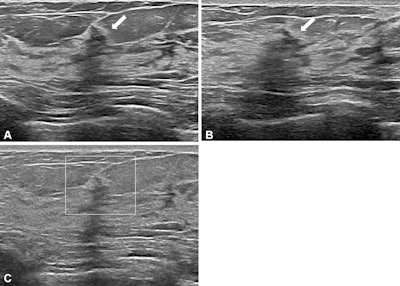

Images depict a 50-year-old woman with a lesion detected during screening ultrasound. (A) Transverse and (B) longitudinal images reveal a 0.5-cm hypoechoic lesion (arrow) in the left breast. (C) Transverse color Doppler ultrasound image does not show an increase in vascularity. Two readers classified the lesion as a mass, whereas two others categorized it as a nonmass lesion, leading to its designation as a controversial nonmass lesion. Ultrasound-guided core needle biopsy and subsequent pathologic examination confirmed a nonproliferative breast change.Images depict a 50-year-old woman with a lesion detected during screening ultrasound. (A) Transverse and (B) longitudinal images reveal a 0.5-cm hypoechoic lesion (arrow) in the left breast. (C) Transverse color Doppler ultrasound image does not show an increase in vascularity. Two readers classified the lesion as a mass, whereas two others categorized it as a nonmass lesion, leading to its designation as a controversial nonmass lesion. Ultrasound-guided core needle biopsy and subsequent pathologic examination confirmed a nonproliferative breast change.RSNA